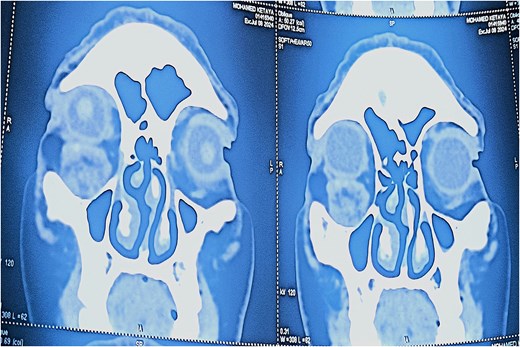

Angio-computed tomography (CT) imaging revealed a well-circumscribed mass measuring 22 × 24 × 18 mm with peripheral contrast enhancement, consistent with a vascularized lesion. Magnetic resonance imaging (MRI) was not performed due to financial limitations. The lesion did not show signs of invasion into adjacent structures (Figs 3 and 4).

Axial CT scan (soft tissue window) revealing a well-defined, ovoid lesion with peripheral contrast enhancement in the inferior orbital region.

Coronal CT scan showing the subcutaneous location of the tumor with no invasion of adjacent structures.

Radiologically, the angio-CT revealed a well-circumscribed mass measuring 22 × 24 × 18 mm with peripheral contrast enhancement, typical for vascular tumors [4]. This peripheral pattern likely corresponds to the rich vascular capsule and differentiates it from other lesions exhibiting homogeneous enhancement. Unfortunately, MRI was not available for this patient due to economic constraints, representing a limitation of this report. MRI would have allowed better tissue characterization and vascular mapping, aiding preoperative planning [5].

The discrepancy between the clinical (15 mm), histopathological (15 × 10 mm), and imaging (22 × 24 × 18 mm) tumor sizes can be attributed to the peritumoral vascular and connective tissue extension captured by imaging modalities but not measured clinically or histologically. This is consistent with vascular tumor behavior, where the radiological extent may exceed the gross tumor size [6].